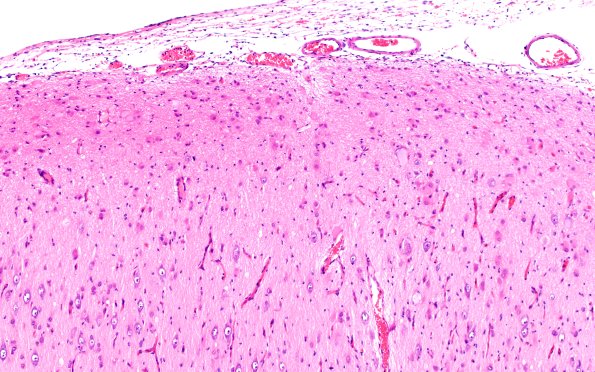

Washington University Experience | DEVELOPMENTAL MALFORMATIONS | Tuberous Sclerosis | 16B3 Tuber (Case 16) H&E 10X

The normal cortical pattern is replaced by disorganized dyslaminate cortex characterized by large dysmorphic neurons in superficial cortical layers and numerous, occasionally binucleate, astrocytes and ballooned cells with indeterminate origin with neuronal nuclei and glassy “glial” cytoplasm. (H&E)